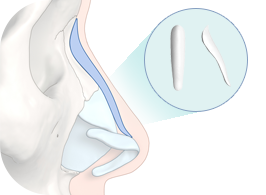

This is 1:1 customized rhinoplasty that allows you to create the most suitable implant for your nose by using 3D printer to create the patient’s skeleton, cartilage, skin tissue, and muscle with data obtained from 3D-ct images.

Because it is possible to manufacture a customized implant that fits perfectly to the nasal bone, it is safe and there is little worry about reoperation as it significantly reduces side effects such as bending, silicone seepage, and lifting.

4Custom Nose Implant

A custom-designed, custom-made nose implant for patients is made with a 3D printer.